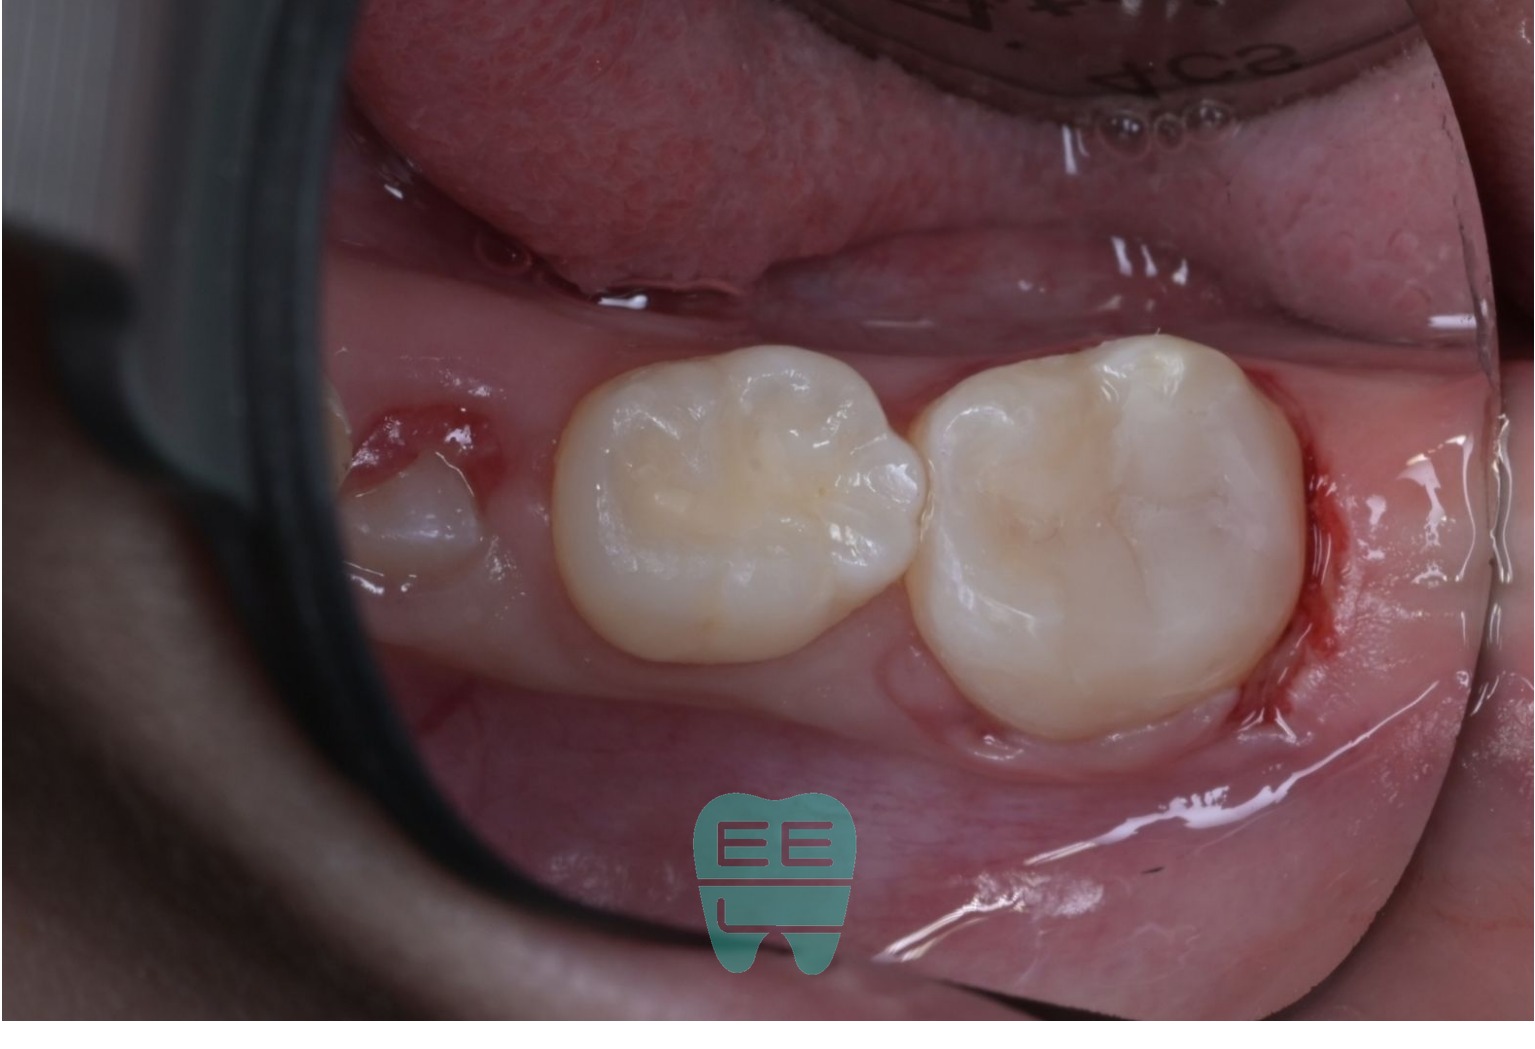

10. 치료 완료: 교합조정과 연마

교합조정과 연마를 마친 최종 모습입니다. 처음 들떠있던 레진과는 완전히 다릅니다. 주변 치아와 자연스럽게 어우러지는 형태와 색감, 그리고 정확한 교합이 확보되었습니다.